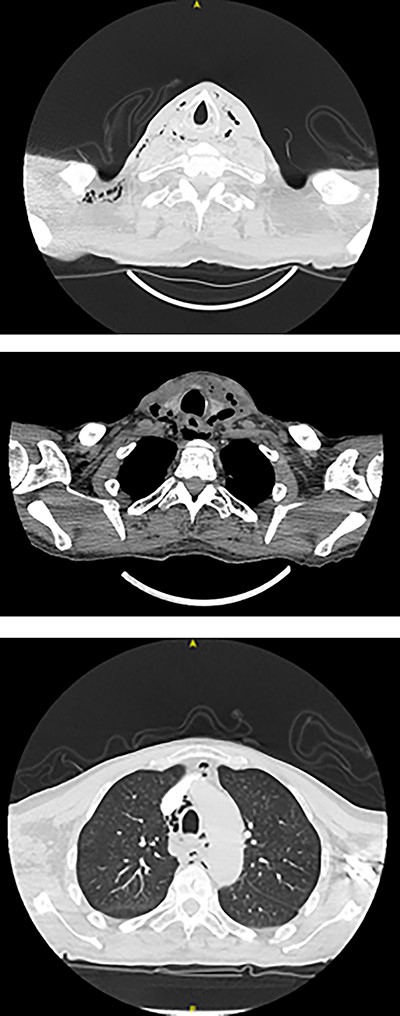

Full blood count, renal function and coagulation profile were within normal limits. C-Reactive protein was mildly raised at 73 mg/l. Neck axial contrast enhanced computer tomography (CT) scan was consistent with significant paraesophageal gas and mediastinitis (Fig. 1). Magnetic resonance imaging (MRI) suggested an enhancing collection from the left parapharyngeal space extending to the mediastinum (Fig. 2). Intravenous Fluconazole was added.

Sagittal plane CT neck and thorax with oral contrast showing significant parapharyngeal gas.

Axial planes CT neck and thorax showing left parapharyngeal abscess with tracking into the prevertebral space, significant progression of air pockets in mediastinal and cervical soft tissue extending to right axillary region.